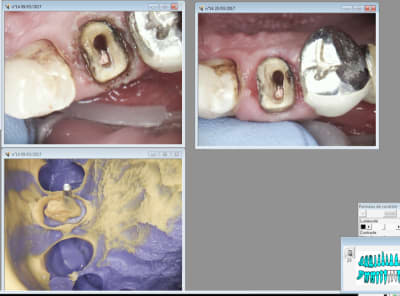

20/03/2017 à 09h54

Celle la ca saignait un peu. -)

Il faudrait que j'arrete de préparer trop sous gingival. Un réflexe à perdre.

Tiens suite de mon Ic à 4 pattes empreinte prise le 9 03 et pose aujourd'hui. Aspect de la gencive encourageant après le coup de laser.

J'ai d'ailleurs récidivé pour l'empreinte de la couronne. -)

Cette 14 pas trop mal.